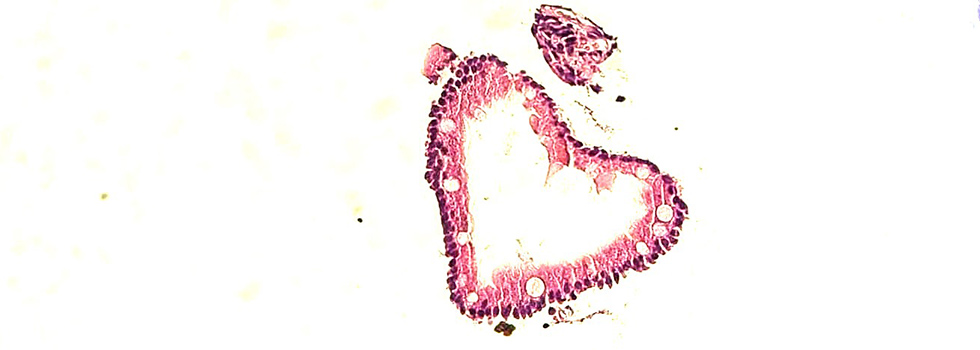

- Analyse: Unsere Fachärzte für Pathologie untersuchen die Proben unter dem Mikroskop und führen gegebenenfalls molekularpathologische Tests durch, um genauere Diagnosen zu stellen.